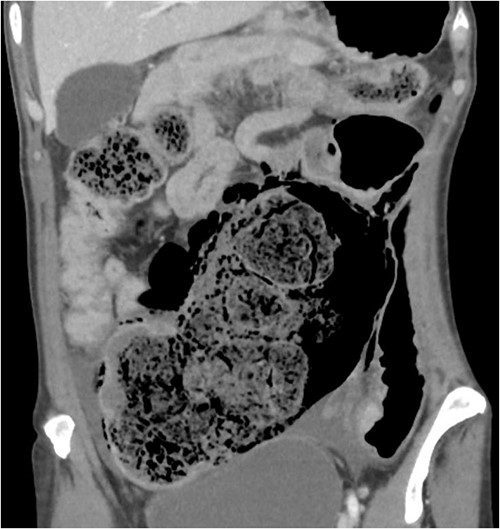

On CT of her abdomen and pelvis, there was a large volume of pneumoperitoneum and a massive sigmoid faecaloma suggestive of stercoral perforation associated with ischaemic changes (Fig. 1). She underwent emergency laparotomy, which identified a grossly dilated and redundant sigmoid colon impacted with a large, inspissated faecaloma >15 cm in diameter (see Figs 2 and 3). The perforation was identified in the mid to distal sigmoid colon with evidence of necrosis of the wall. A Hartmann’s procedure and extensive washout was performed. Post-operatively, the patient required vasopressor support for septic shock in intensive care, as well as granulocyte colony stimulating factor (G-CSF) to help in the management of her febrile neutropaenia. Her Clozapine was suspended for several days due to her neutropenia. She was given G-CSF to improve her neutropenia to improve her chances of survival as it known that immunocompromised patients with sepsis have worse prognosis [9]. Fortunately, the patient recovered well post-operatively and was discharged to rehabilitation on day 10.

CT abdomen pelvis demonstrating inspissated with faecaloma with pneumatosis and adjacent free gas.

In this case, the patient met all four criteria. Furthermore, Fig. 1 clearly shows that the pressure effect from an impacted inspissated faecaloma can cause necrosis of the bowel wall in the absence of diverticulitis, neoplastic lesion and adhesions as the adjacent bowel was healthy without other disease processes. This case report supports that stercoral perforation from chronic constipation is a real entity. The old adage that constipation can kill is not a myth.